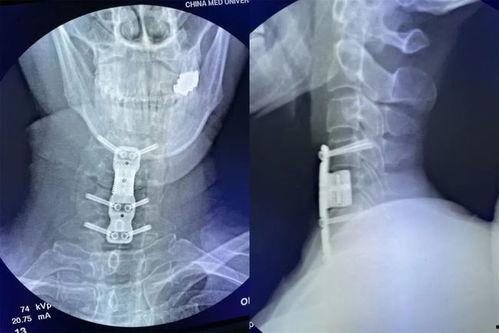

为了恢复颈椎的稳定性,医生会在切除病变组织后,植入人工椎间盘或椎体。这些植入物可以模拟正常椎间盘的功能,减轻颈椎的压力。

手术完成后,医生会逐层缝合切口,并包扎。术后,患者会进入恢复室,接受医生的观察和护理。